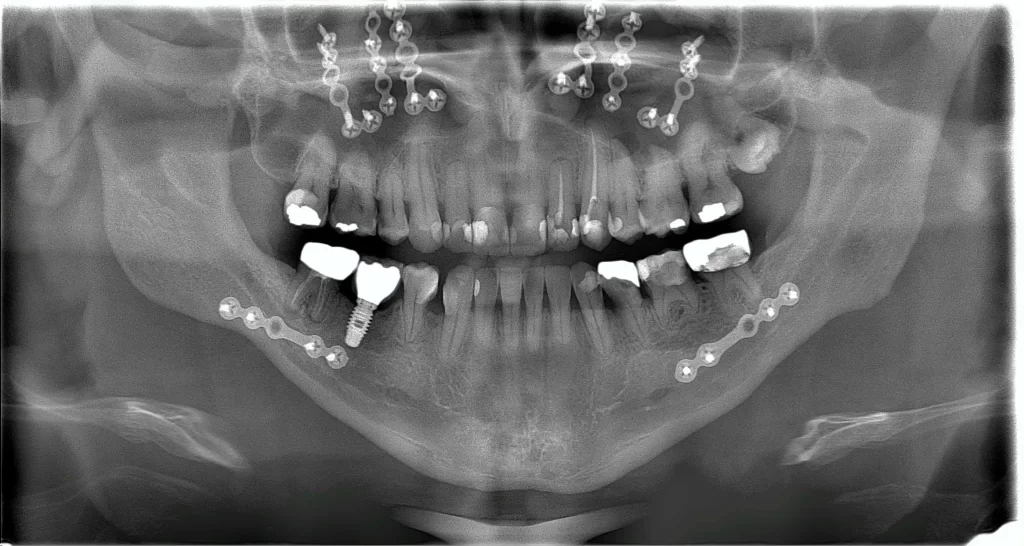

Jaw Orthognathic Surgery

Jaw surgery to correct long and short jaws is one of the basic tenants of Oral & Maxillofacial Surgery. Oral & Maxillofacial surgeons are extremely well trained in this area. The success of such surgeries not only requires proper planning of the actual bone surgery itself but also a very good knowledge of the dental occlusion.

Most jaw surgeries are indicated when the orthodontist (braces doctor) finds that the teeth cannot be moved to meet despite the best efforts. This can be due to a larger difference than usual of the distance between the upper and lower jaw arches. There are also cases when the upper or lower jaw arches are developed in an asymmetric manner. These are indications for jaw (bone) surgery.